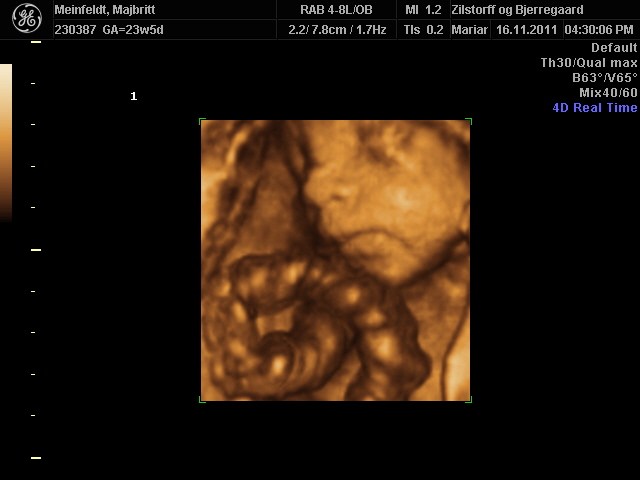

Hvor er det dejligt for jer, at have fået set jeres skønne børn.. Der er bare nogle rigtig fine billeder..

Vi har godt nok valgt ikke at få en 3D skanning, men man bliver helt varm om hjertet når man ser de fine billeder.. Og som der er skrevet længere oppe, der er jo lang tid til marts